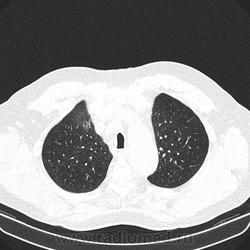

Альвеолярное кровоизлияние.

Полисегментарная пневмония.

оказалось ТЭЛА.

эту пневмонию вылечили, через некоторое время пациент поступил с подобной картиной в другом легком.

потом нашли тромб в артериях н/конечностей.